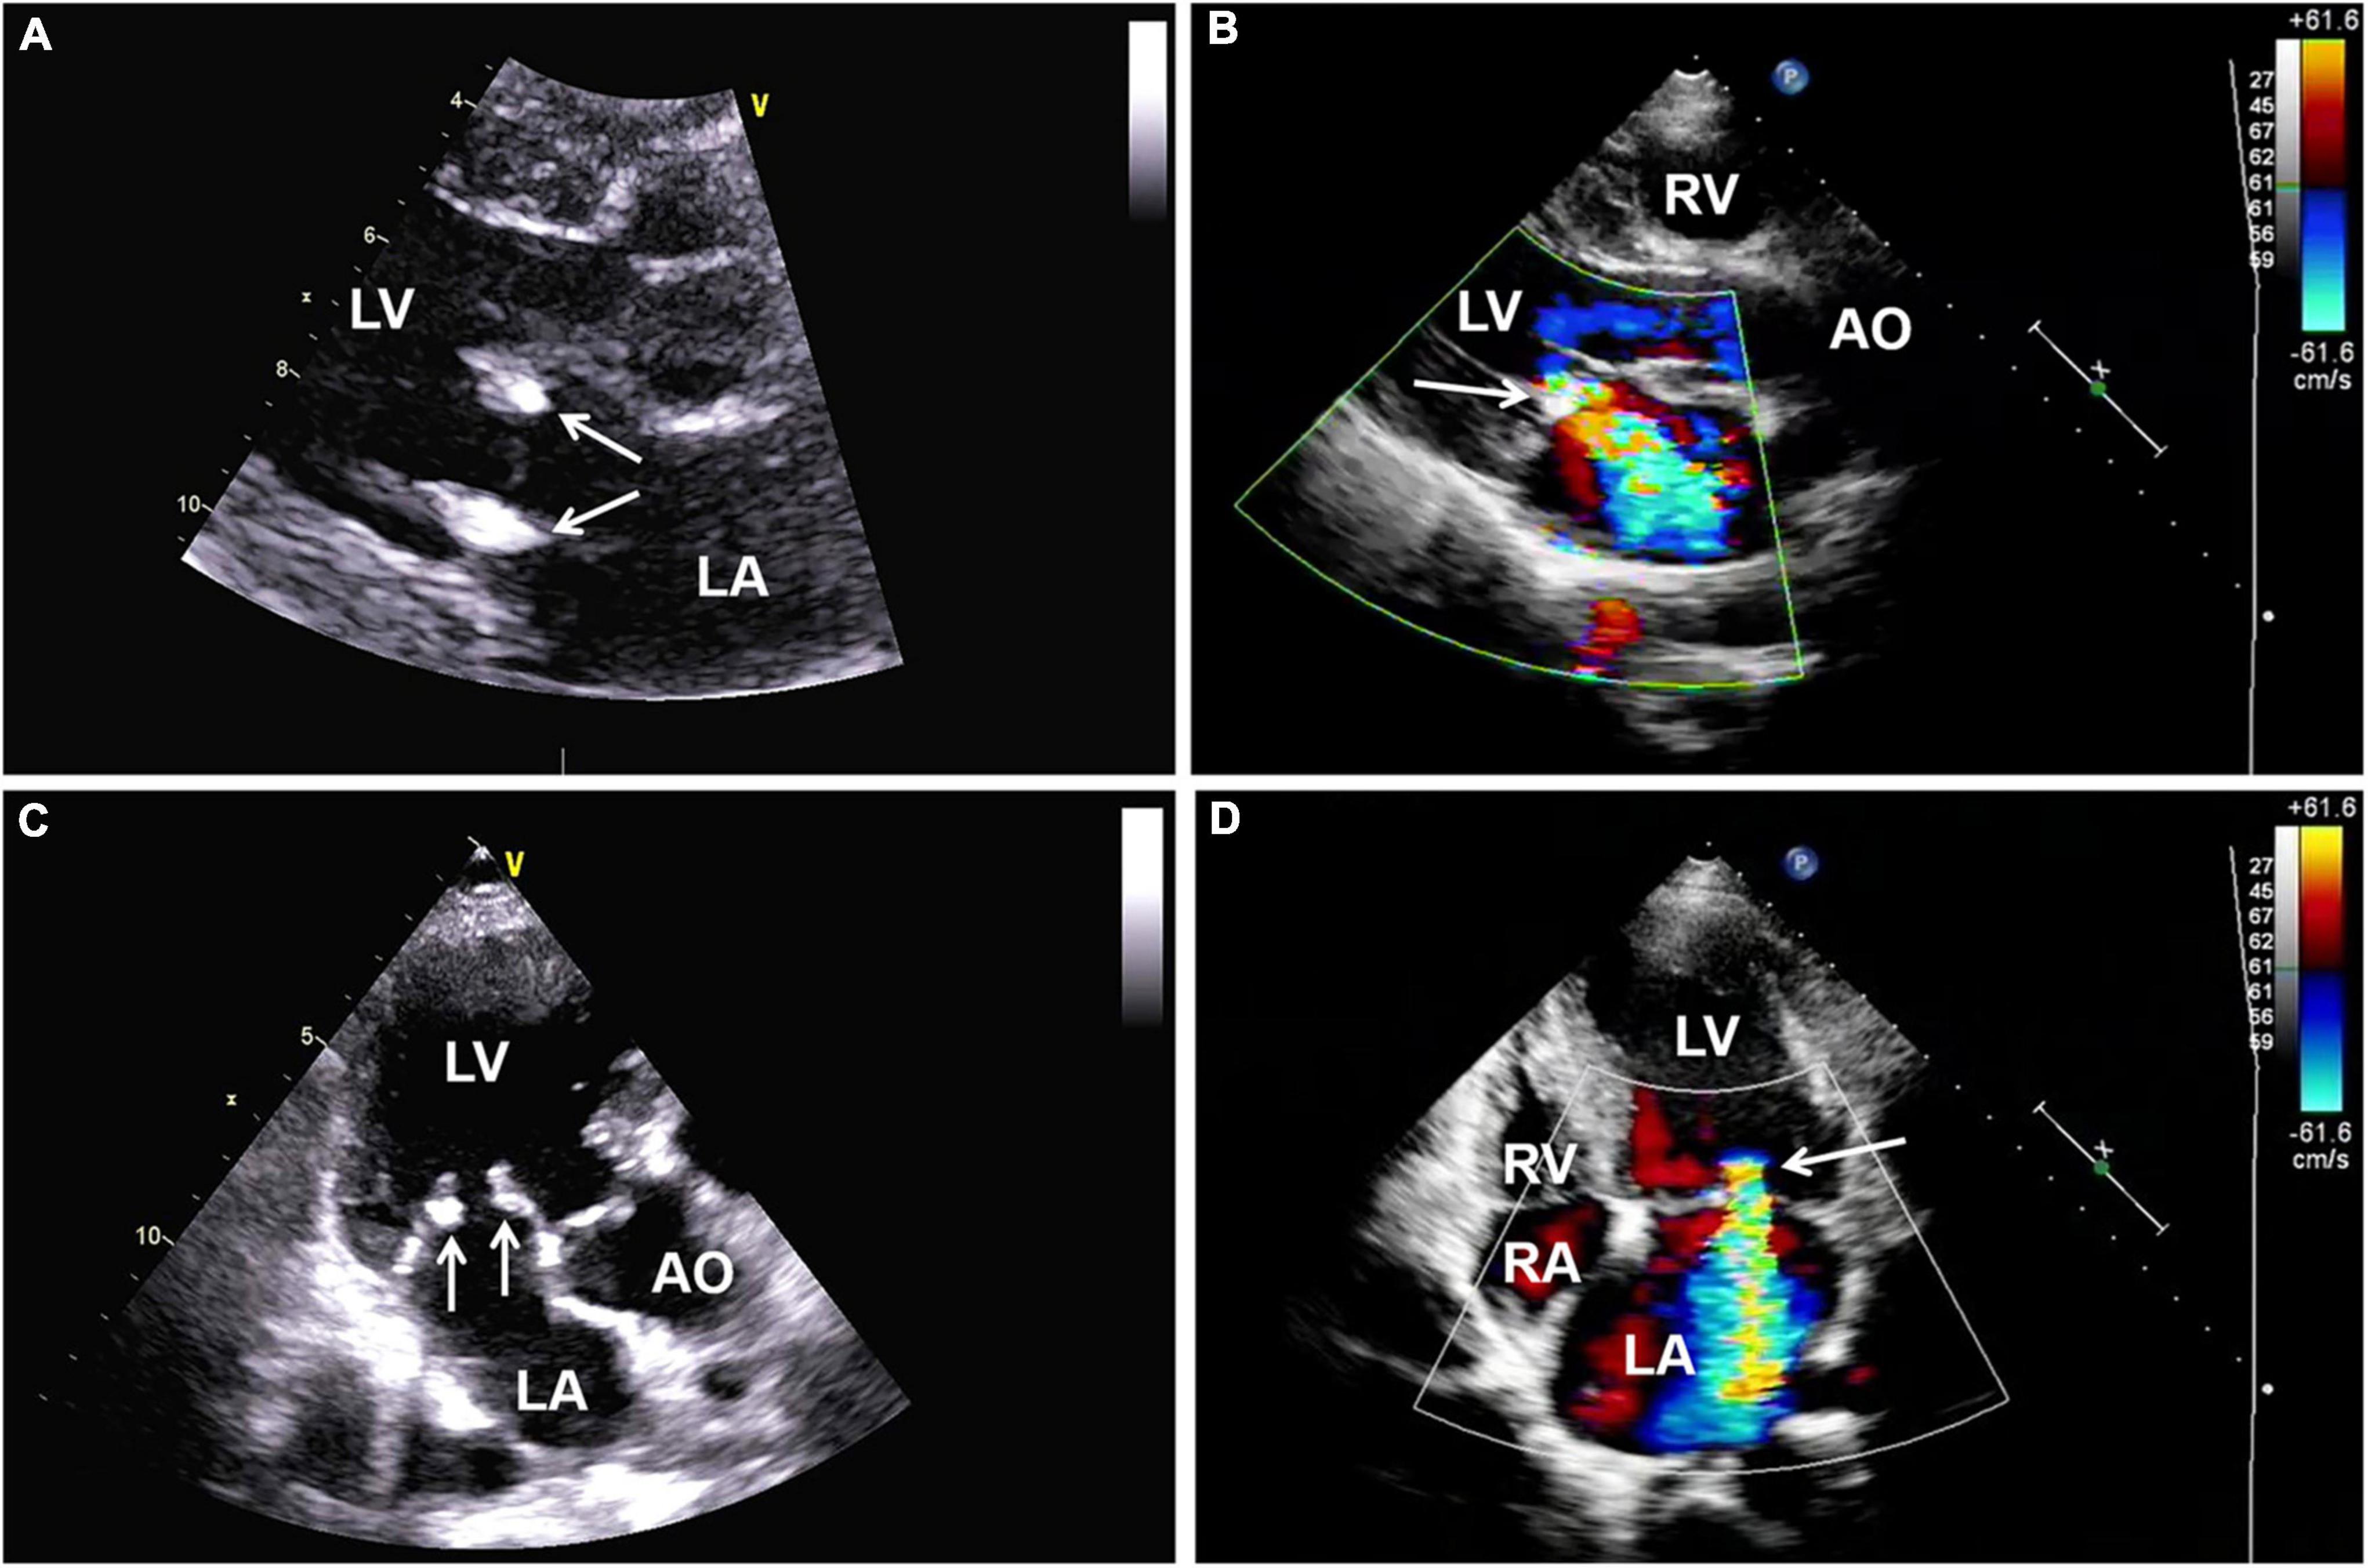

Magnetic resonance imaging (MRI) of the brain was then performed, showing multiple infarctions and softening lesions in the right thalamus, paraventricular area, and cerebellar hemisphere (Figure 1). Magnetic resonance arteriography (MRA) showed right middle cerebral artery occlusion. A carotid ultrasound scan was normal. Transthoracic echocardiogram (TTE) demonstrated that the cusps of the anterior and posterior mitral valve leaflets were thickened. Additionally, verrucous and nodular vegetations with heterogeneous echo-density could be seen at the commissural border of both mitral valve leaflets (Figures 2A,C). The vegetations were firmly attached to the surface of the valve without obvious independent motion. Mild to moderate mitral regurgitation was detected at the central commissure when the valve closed (Figures 2B,D) with an effective regurgitant orifice area (EROA) of 0.25 cm2 and the regurgitant volume of 36 mL. The other valves were morphologically normal. The left ventricular function was normal, with a left ventricular ejection fraction (LVEF) of 60%. Repeated blood cultures were negative, and the patient had no recent history of fever. Considering these findings, the patient was diagnosed with primary APS, LSE, and cerebral infarction. Symptomatic treatment was provided to her during hospital admission with sufficient low molecular weight heparin and warfarin anticoagulation. Oral prednisolone acetate (15 mg/day) and warfarin were administered after her discharge.

FIGURE 2

(A,C) Transthoracic echocardiography showing thickened mitral valve leaflets with verrucous, nodular, heterogeneous echoic vegetations located on the commissural border of both leaflet tips (arrows). (B,D) Color Doppler imaging revealing mild to moderate mitral regurgitation (arrow). AO, aorta; LA, left atrium; LV, left ventricle; RA, right atrium; RV, right ventricle; TTE, transthoracic echocardiography.